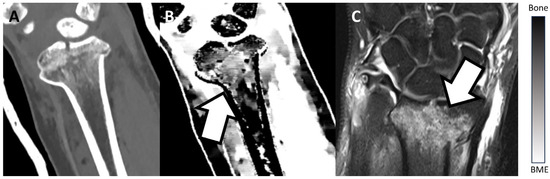

Figure 2 and Figure 3 show examples of BME on TMD images in different locations. Figure 2 presents an example of a fractured proximal tibia on conventional CT images and the TMD tool, whereas Figure 3 shows a fractured distal radius.

Figure 3.

Fractured distal radius of a patient on a conventional CT image (A), on the TMD tool (B), and the corresponding MRI (C). The TMD tool and the corresponding MRI clearly show a BME (white arrow), whereas the conventional CT image does not depict the BME. Additionally, a bar chart shows the density/intensity levels between normal bone and BME.